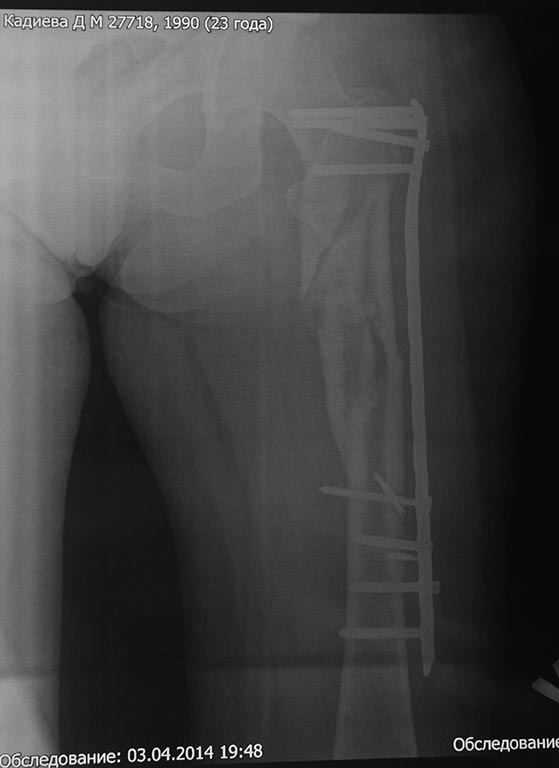

Предполагался БИОС бедренной кости, однако из-за отсутствия в больнице

современных имплантов (угадайте с 3-х раз- почему?)и средств у больной

был выполнен 22.01.14 малоинвазивный остеосинтез проксимального отдела

бедра чем Бог послал (каким-то чудом оказавшаяся у нас дистальная

бедренная пластина "Деост", не б/у) (см. снимки)-критика принимается.

П/операционный период гладкий. Выписана с рекомендацией начать нагрузку